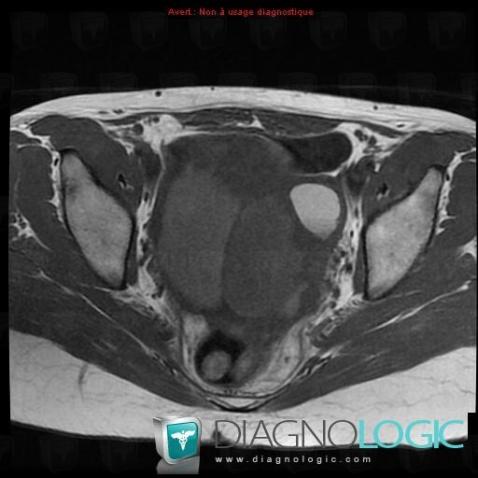

Serous cysteadenocarcinoma, Adnexa / Ovary fallopian tube, Pelvis / Perineum, MRI

Here is the specific information in the key image above:

- Diagnosis Serous cysteadenocarcinoma (link to Serous ovarian tumor), Location(s) Adnexa / Ovary fallopian tube, with gamuts T2 WI hyperintense adnexal mass, Cystic adnexal massPelvis / Perineum, with gamuts Large pelvic mass, Cystic pelvic mass